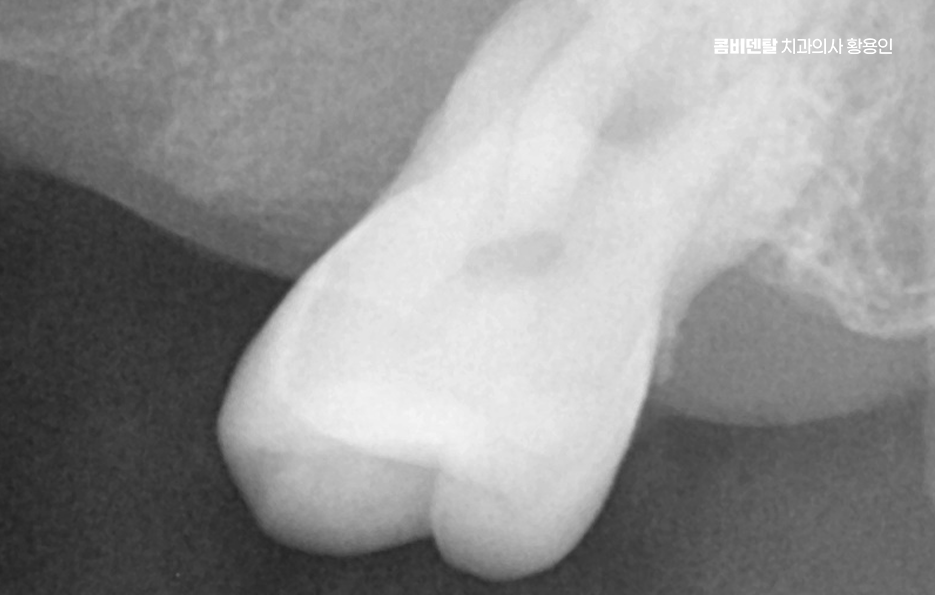

50대임플란트 치료는 시작 전에 정밀한 진단이 선행되어야 하는데 단순히 빈자리만 보고 이 자리에 임플란트를 하나씩 심는 방식이 아니라 턱뼈 상태, 잇몸 높이, 씹는 힘의 분포, 전체 교합의 불균형까지 전부 고려해야 안정적이고 오래 가는 치료가 될 수 있어요

그래서 CT 촬영으로 턱뼈의 두께, 밀도, 신경 위치를 정밀하게 확인하고 각 임플란트의 위치와 각도를 계획해야 하며 50대는 전신 건강 상태도 함께 고려해야 하는데 당뇨, 고혈압, 골다공증 같은 만성 질환이 있는 경우에는 임플란트 치료 시 잇몸 치유 속도나 골융합 반응이 다를 수 있기 때문에, 반드시 의료진과의 충분한 상담이 필요하고 약물 복용 여부나 치유 능력 등을 고려해 치료 시기와 방식을 1:1 맞춤형으로 계획하실 필요가 있어요